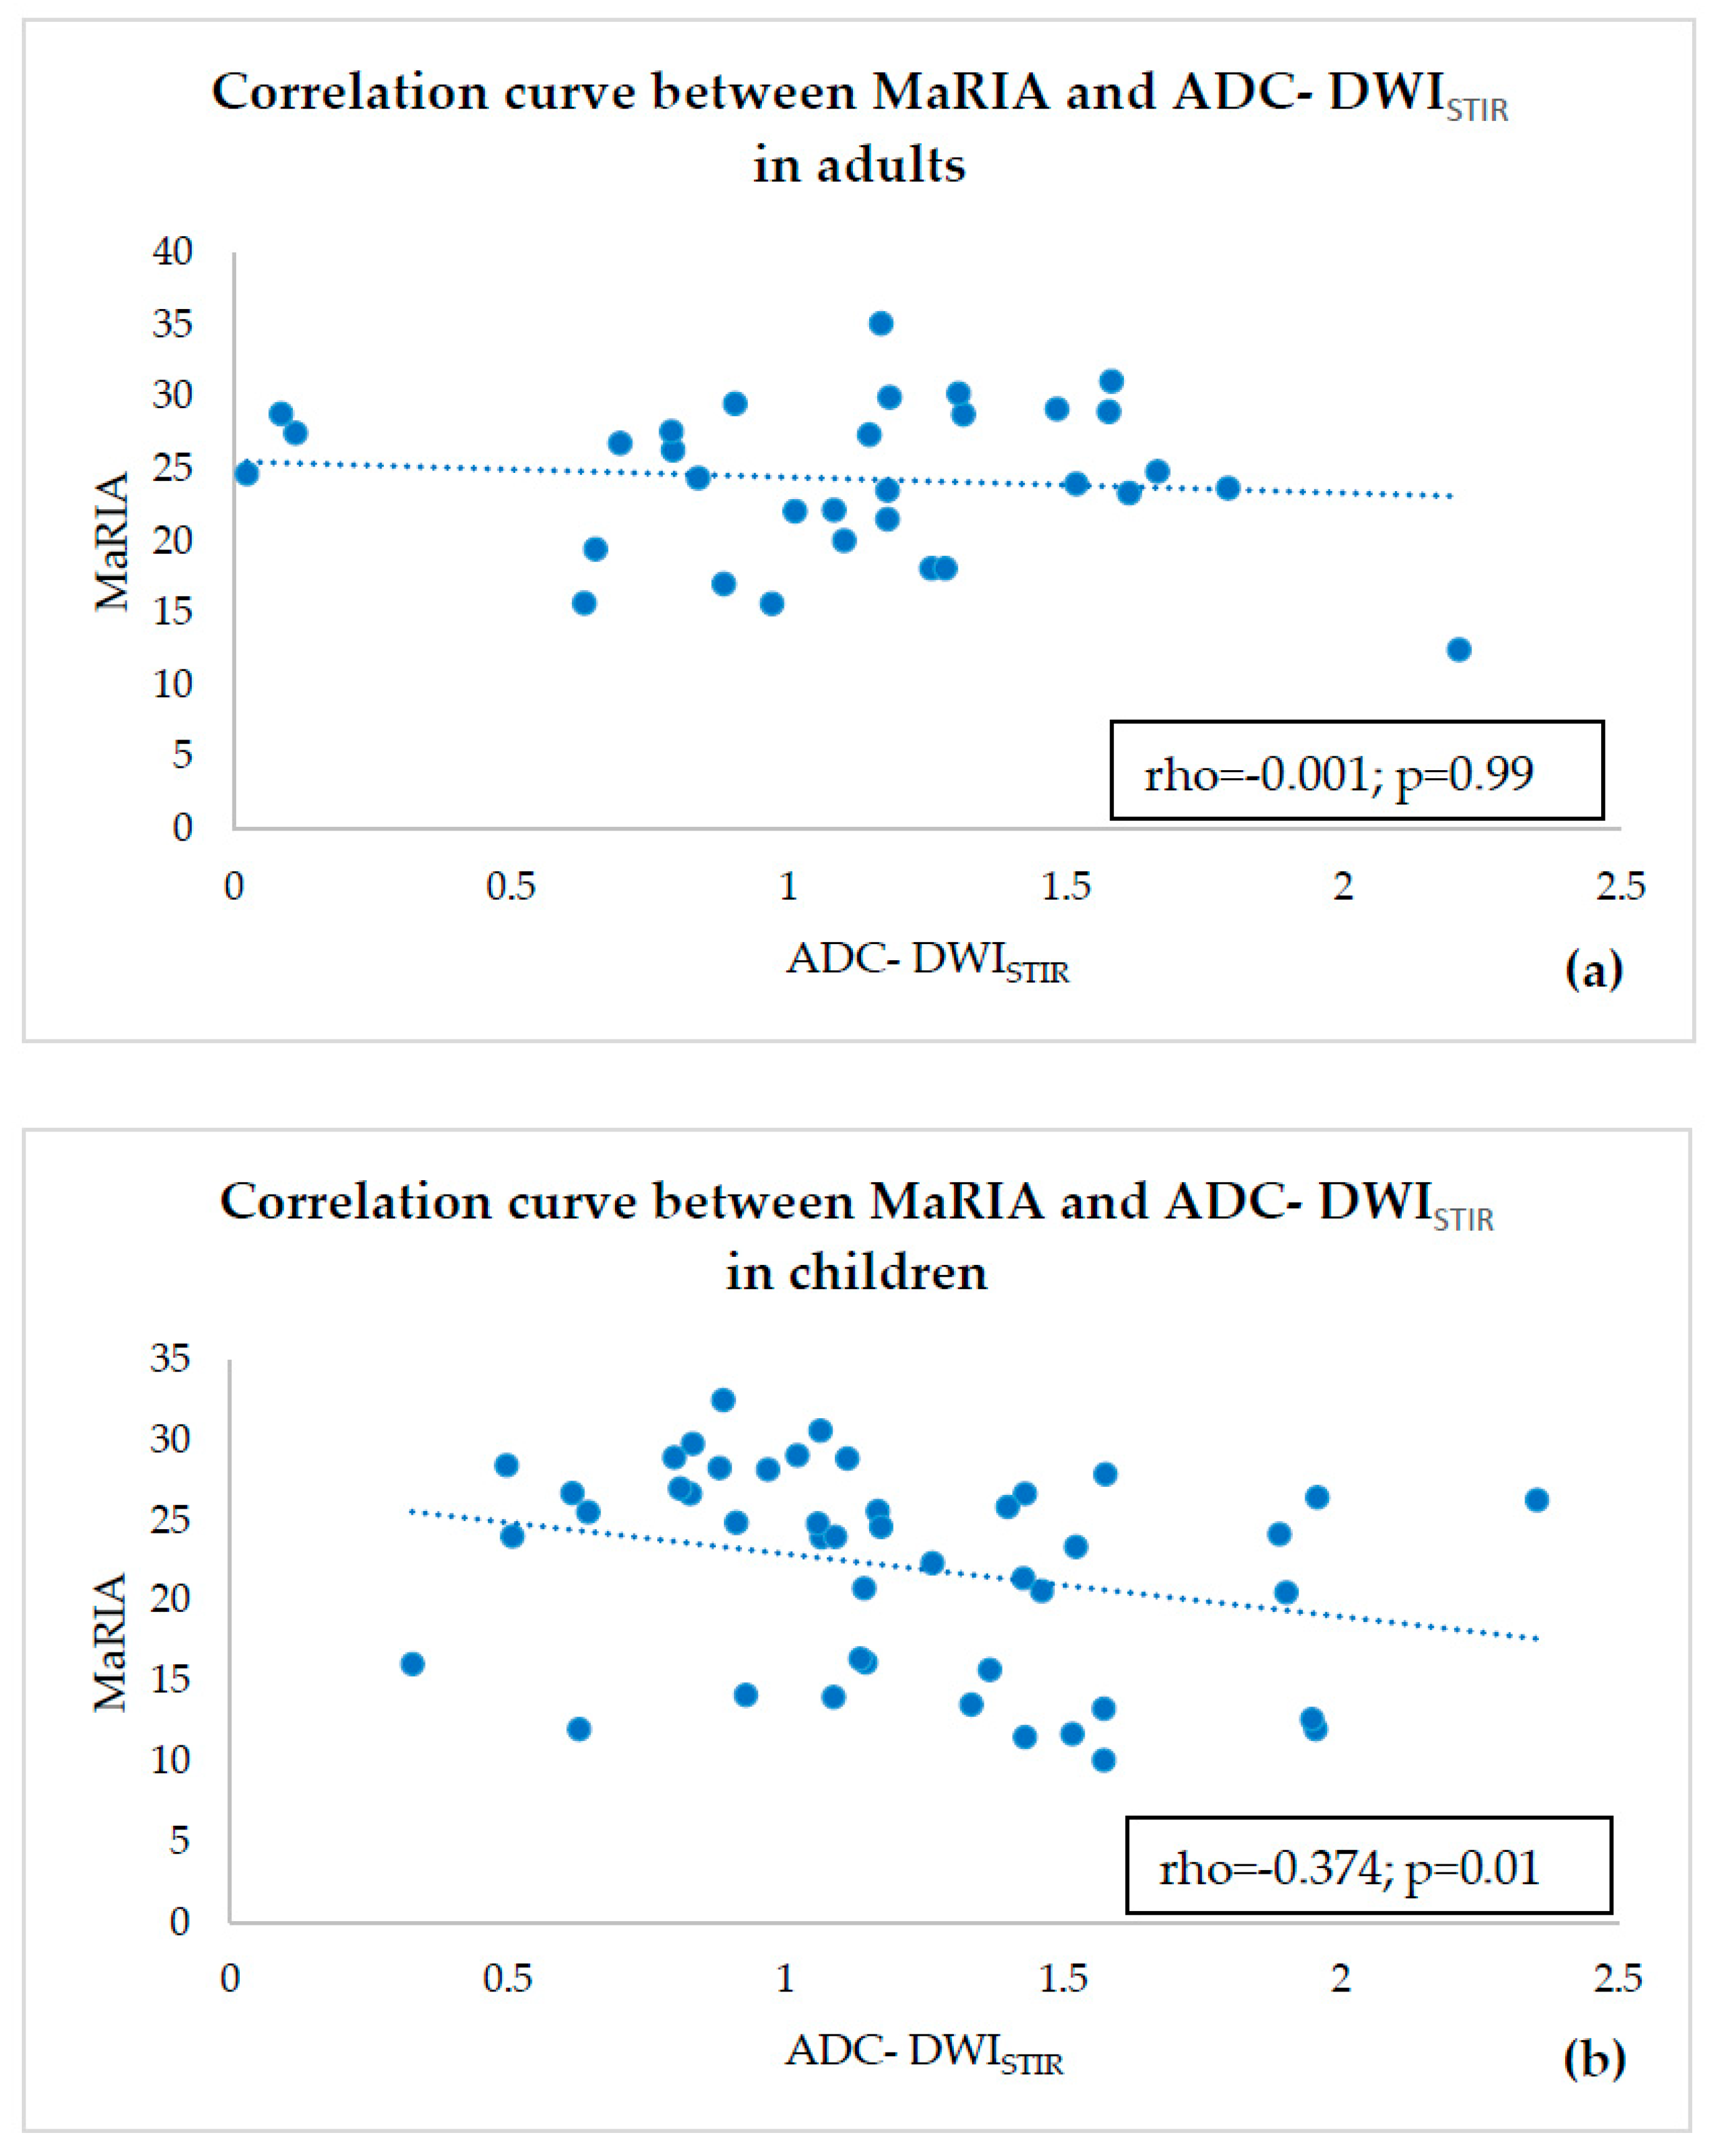

- estimating correlations of ADC-DWISPIR and ADC-DWISTIR values with the corresponding MaRIA, calculated from the contrast–enhanced sequences within the same bowel segments,

- ADC values of both adults and children were compared within a single fat suppression technique, and we observed statistically significant ADC-DWISPIR difference between adults and children (1.31 × 10−3 mm2/s, SD 0.29, vs. 1.16 × 10−3 mm2/s, SD 0.31; p = 0.02), with 12.12% lower ADC values in children compared to adults, but no statistically significant difference between the ADC-DWISTIR values in adults and children (1.09 × 10−3 mm2/s, SD 0.49, vs. 1.20 mm2/s × 10−3, SD 0.44; p = 0.38);

- both DWISPIR and DWISTIR techniques were compared within one patient group, both in adults and children. In this case, the analysis showed difference of 16.73% between ADC-DWISPIR and ADC-DWISTIR values in adults, being lower in DWISTIR (1.31 × 10−3 mm2/s, SD 0.29, vs. 1.09 × 10−3 mm2/s, SD 0.49; p = 0.03), but did not show difference between ADC-DWISPIR and ADC-DWISTIR values in the children’s group (1.16 mm2/s × 10−3, SD 0.31, vs. 1.20 × 10−3 mm2/s, SD 0.44, p = 0.97).